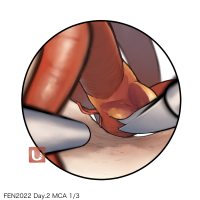

FEN2022シリーズ